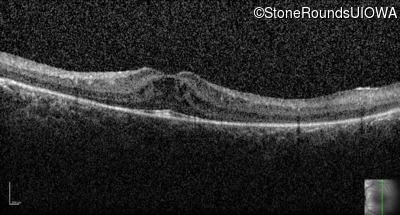

Optical Coherence Tomography - Left - 20/32

Exemplar / OCT Stack